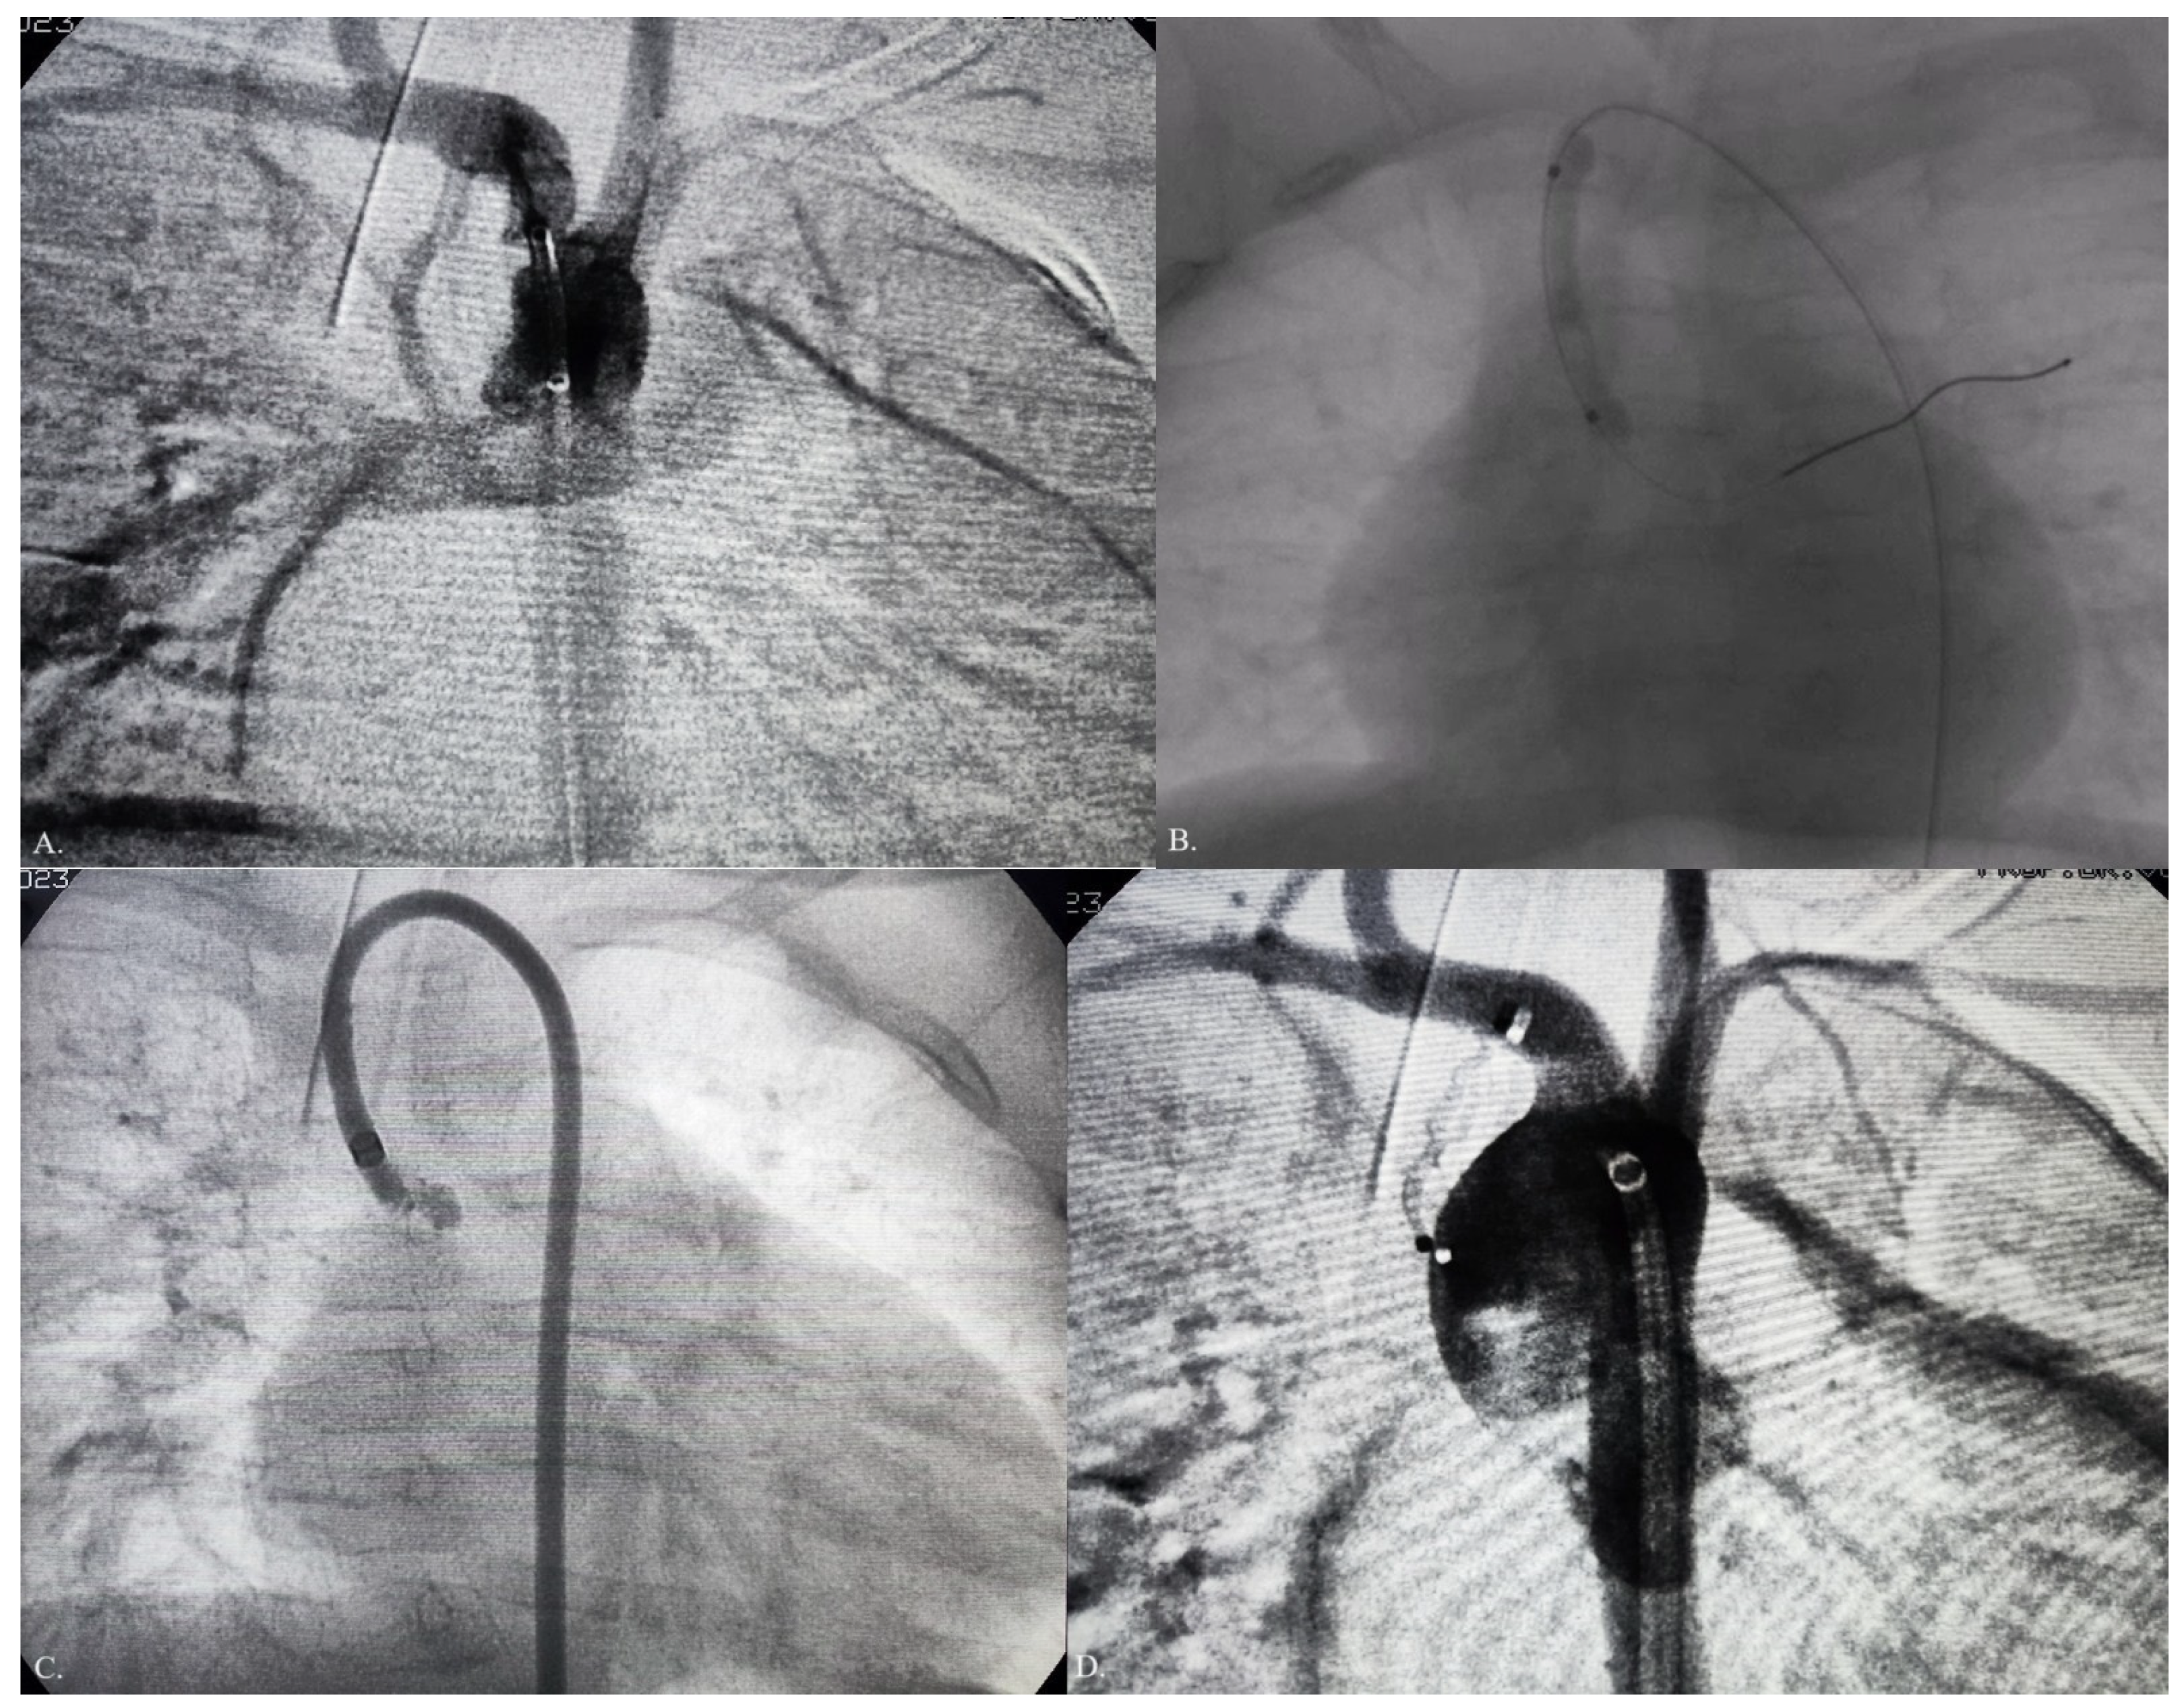

2. Case Report